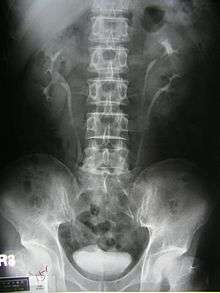

Duplicated ureter

Duplicated ureter or Duplex Collecting System is a congenital condition in which the ureteric bud, the embryological origin of the ureter, splits (or arises twice), resulting in two ureters draining a single kidney. It is the most common renal abnormality, occurring in approximately 1% of the population.[1][2] The additional ureter may result in a ureterocele, or an ectopic ureter.